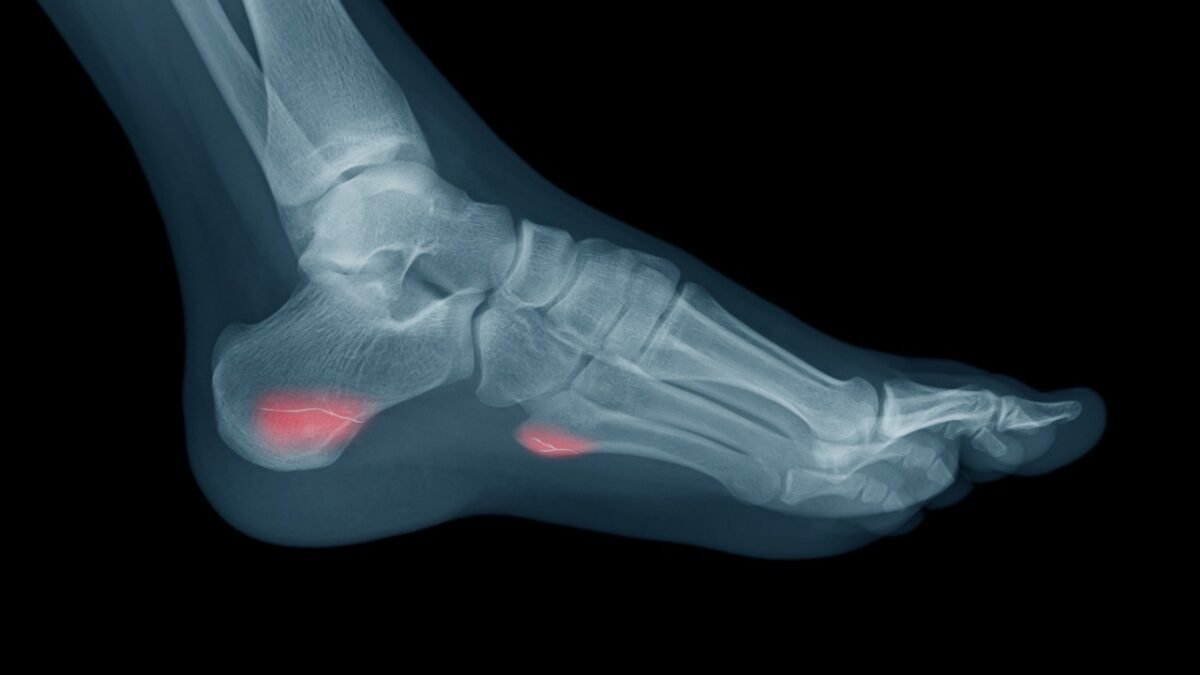

- كسور القدم وكسور الكاحل: شائعة في الرياضات التي تعتمد على الجري والقفز مثل كرة القدم، وغالبًا ما تحدث نتيجة الهبوط الخاطئ.

التعامل السريع مع إصابات العظام والتشخيص الدقيق باستخدام الفحوصات المناسبة عامل أساسي لضمان الالتئام السليم والعودة الآمنة للملاعب.

علاج إصابات العظام

يعتمد علاج إصابات العظام على نوع الكسر ومكانه، وقد يشمل التثبيت باستخدام الجبائر أو الدعامات، أو التدخل الجراحي في الحالات التي تتطلب تثبيتًا داخليًا.

بعد التئام العظام، يُعد العلاج الطبيعي مرحلة أساسية لاستعادة القوة الحركية والقدرة الوظيفية، وضمان عودة الرياضي للملاعب دون مضاعفات.